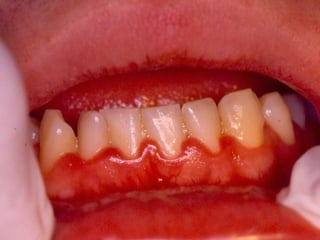

Epidemiologia Hospital Mario Penna – Belo Horizonte Dados socioeconômicos do paciente com Ca de Boca 44,8%  dos pacientes analfabetos 58,9%  dos pacientes com renda inferior a 1 salário mínimo (Abdo, E.N.  et   al. , 2002 )

28 - Paciente apresenta-se ao consultório com alterações gengivais.  Ao final  dessa primeira visita,  sai  com as seguintes instruções: –  Evitar tabaco, álcool e condimentos. –  Fazer bochechos com 1 copo de água quente misturada em quantidades iguais com peróxido de hidrogênio a 3% a cada 2 horas e/ou duas vezes ao dia com solução de clorexidina a 0,12%. –  Exercer as atividades usuais, porém evitar exercícios físicos ou exposições prolongadas ao sol. –  Escovar  delicadamente os dentes para  remoção de resíduos com dentifrício suave.  Bochechos de clorexidina poderão também ser úteis no controle de placa.

Frente a essas instruções, pode-se depreender que ele é portador de: a) Gengivoestomatite herpética aguda. b) Pericoronarite aguda. c) Abscesso periodontal crônico. d) Abscesso gengival. e) Gengivite necrosante ulcerativa aguda.

27 - Paciente com 25 anos de idade, sexo masculino, se queixa de dor na gengiva, mau hálito, gosto metálico e sangramento. Clinicamente observa-se necrose e ulceração interproximal e pseudomembrana fibrinosa. O diagnóstico é: a) Gengivoestomatite herpética. b) Gengivite descamativa. c) Periodontite juvenil. d) Estomatite aftosa recorrente. e) Gengivite ulcerativa necrosante aguda.

28 - Pacienteapresenta-se ao consultório com alterações gengivais. Ao final dessa primeira visita, sai com as seguintes instruções: – Evitar tabaco, álcool e condimentos. – Fazer bochechos com 1 copo de água quente misturada em quantidades iguais com peróxido de hidrogênio a 3% a cada 2 horas e/ou duas vezes ao dia com solução de clorexidina a 0,12%. – Exercer as atividades usuais, porém evitar exercícios físicos ou exposições prolongadas ao sol. – Escovar delicadamente os dentes para remoção de resíduos com dentifrício suave. Bochechos de clorexidina poderão também ser úteis no controle de placa.

Frente a essasinstruções, pode-se depreender que ele é portador de: a) Gengivoestomatite herpética aguda. b) Pericoronarite aguda. c) Abscesso periodontal crônico. d) Abscesso gengival. e) Gengivite necrosante ulcerativa aguda.